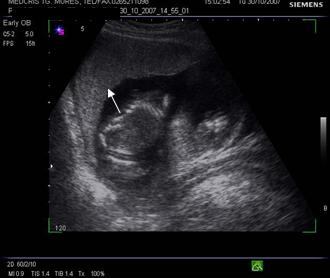

Fig. nr.210. Placenta gr. II la o sarcina de 30 sapt. gestationale, sageata indica proeminenta ondulatiilor dinspre placa choriala , spre placa bazala